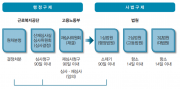

| 2019년 5월 23일 (목) 07:21 | 전공의핸드북 그림62.png (파일) |  |

223 KB | Sjlee | 1 | |